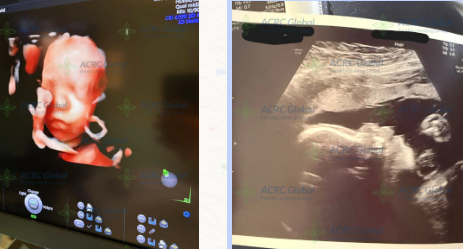

代理母の妊娠経過レポート:妊娠27週の超音波検査(ACRC Surrogacy)

心温まる健診のご報告です。

代理母Kさんが、妊娠27週の胎児超音波検査を無事に終えました。赤ちゃんの発育は順調で、すべての指標が健康的な範囲内にあります。

さらに、赤ちゃんの顔立ちの輪郭もうっすらと確認でき、小さな体をくるりと丸めている様子がとても愛らしく感じられました。